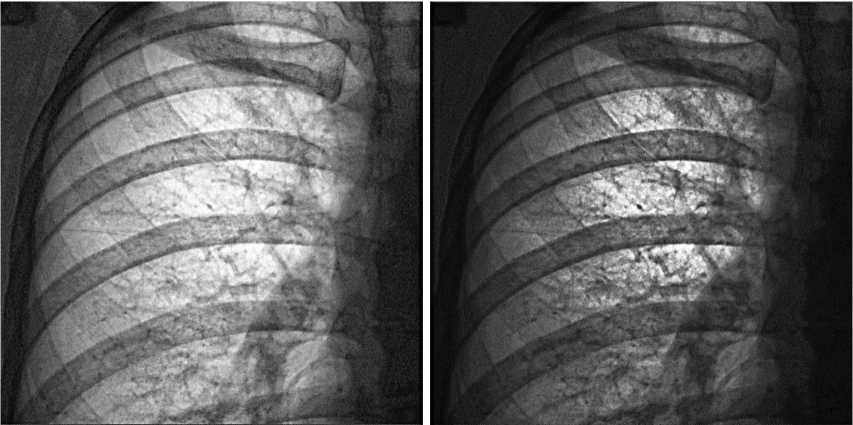

Приведем для наглядности пару примеров применения LUT. На рис. 2 изображен результат применения LUT, сгенерированного по значениям по умолчанию, график функции которой изображен на рис. 1. Следует отметить, что значения по умолчанию не являются оптимальными для мягких тканей, поэтому, произведя некоторую коррекцию параметров, можно получить более подходящий LUT. Рис. 2 служит, скорее, для демонстрации преобразования со стандартными параметрами.

Рис. 2. Слева – исходное изображение, справа – результат применения LUT, полученного при значениях по умолчанию

Fig. 2. The original image is on the left, the result of applying the LUT obtained with default values is on the right